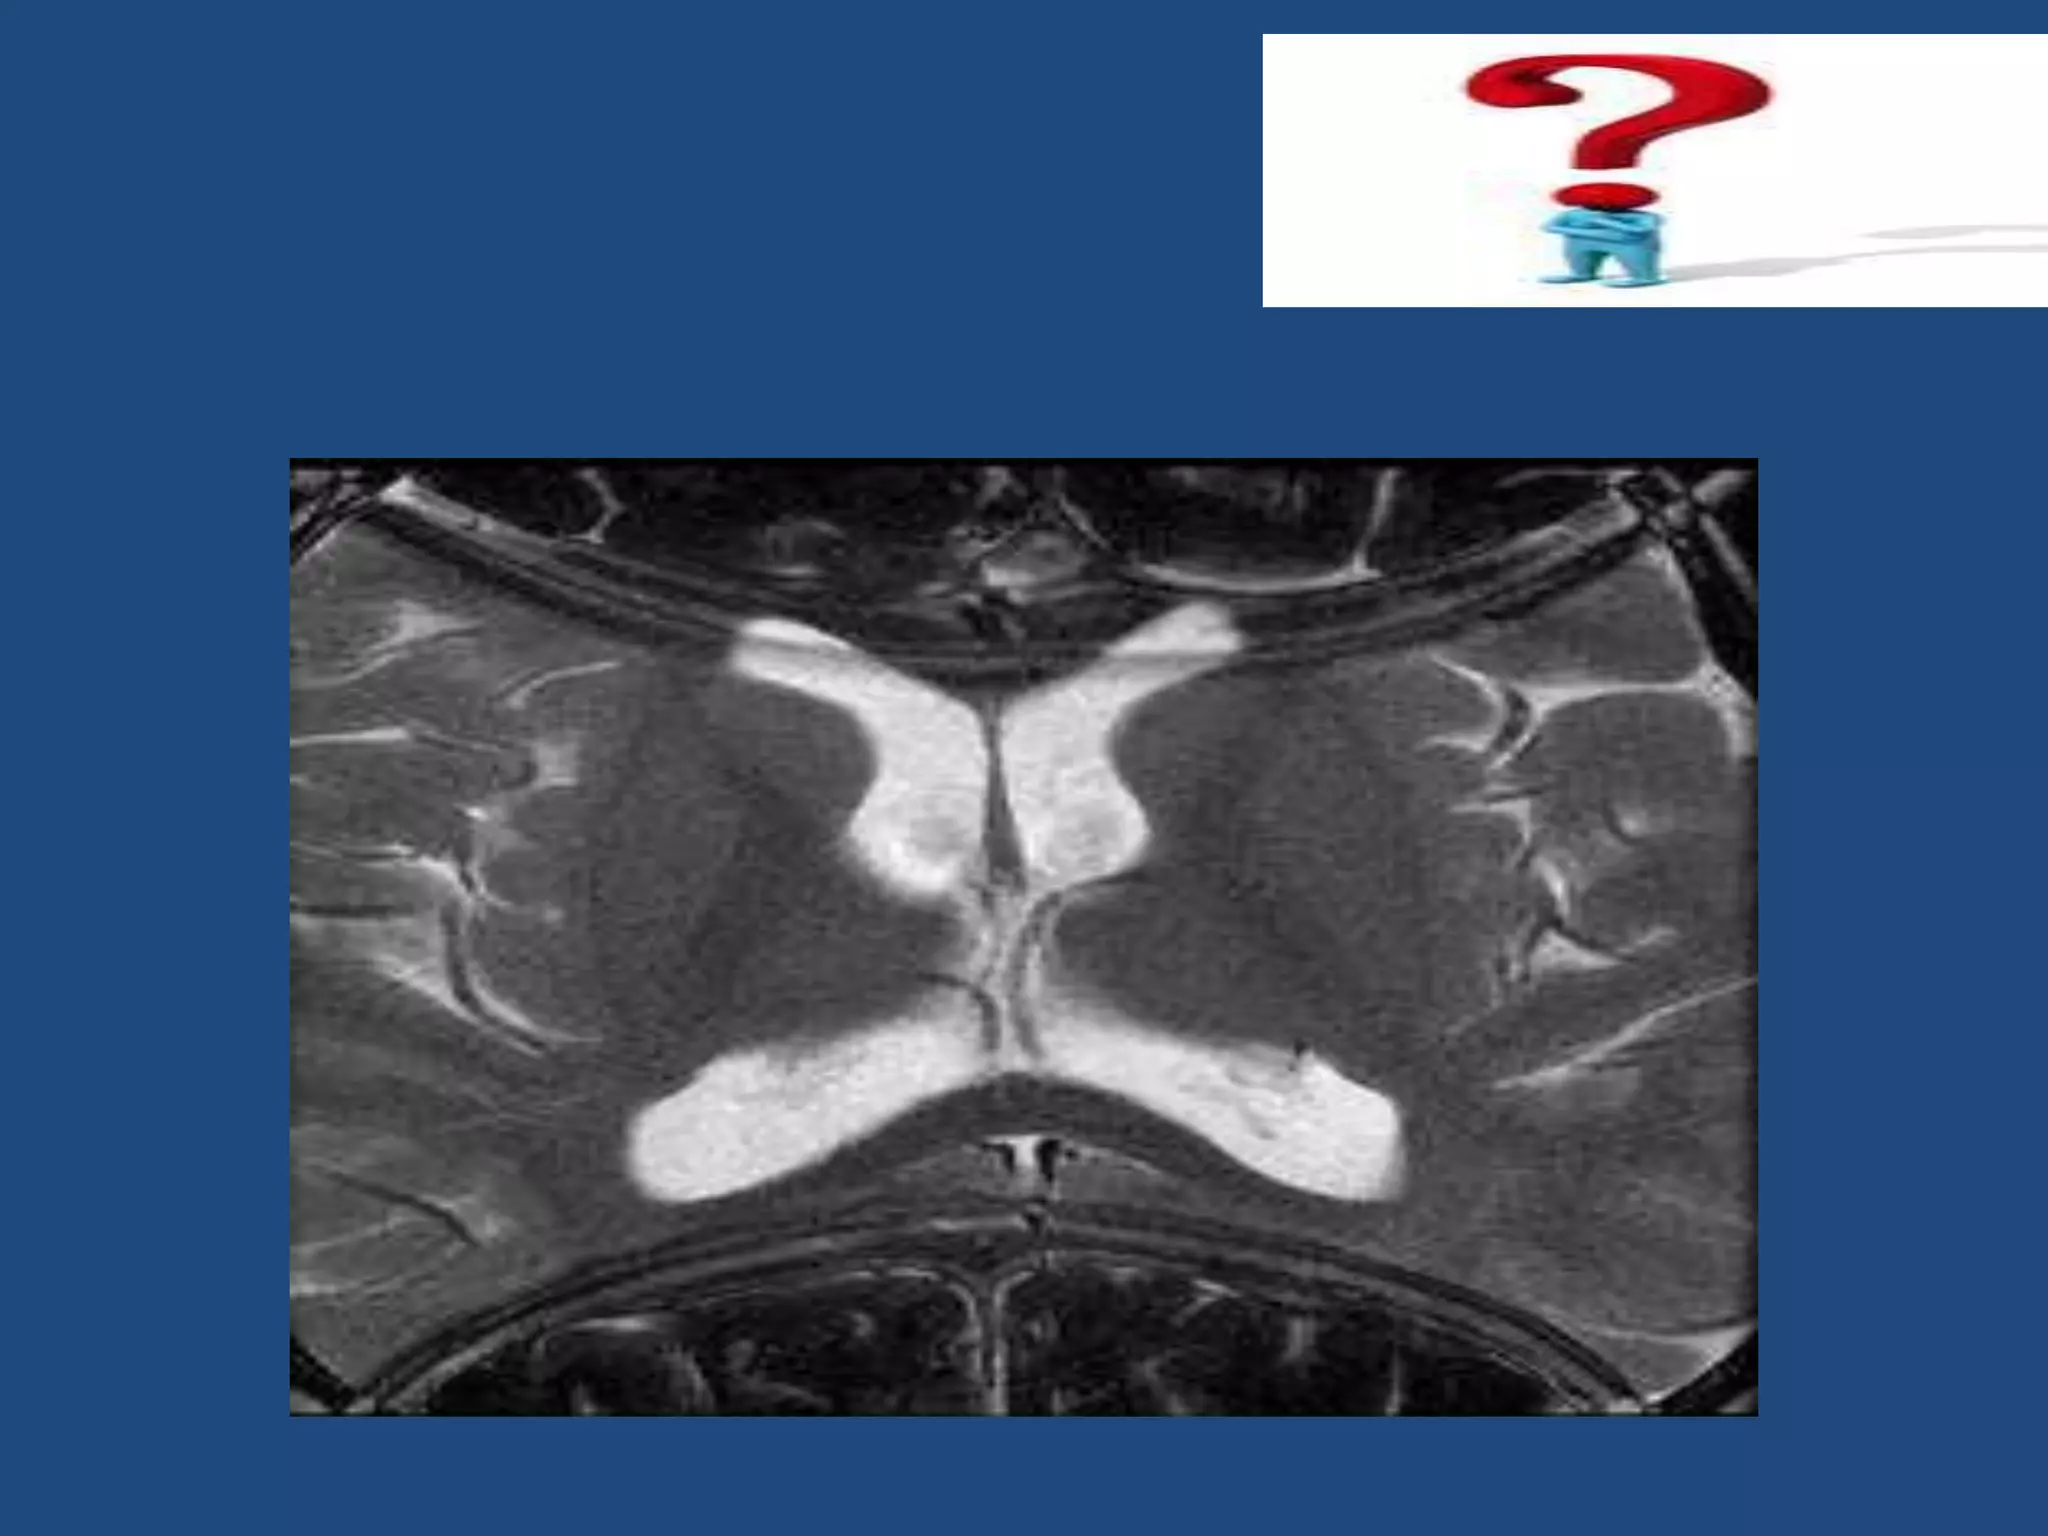

Relaxation Process 1-NMV recoversand realign to B0 this process called "T1 Recovery" 2-Nuclei loose Precessional coherence or dephase and NMV decay in the transverse plane this process called "T2 Decay"

T1 time &T2 Decay are an intrinsic contrast parameter that are inherent to tissue being imaged. T1WI